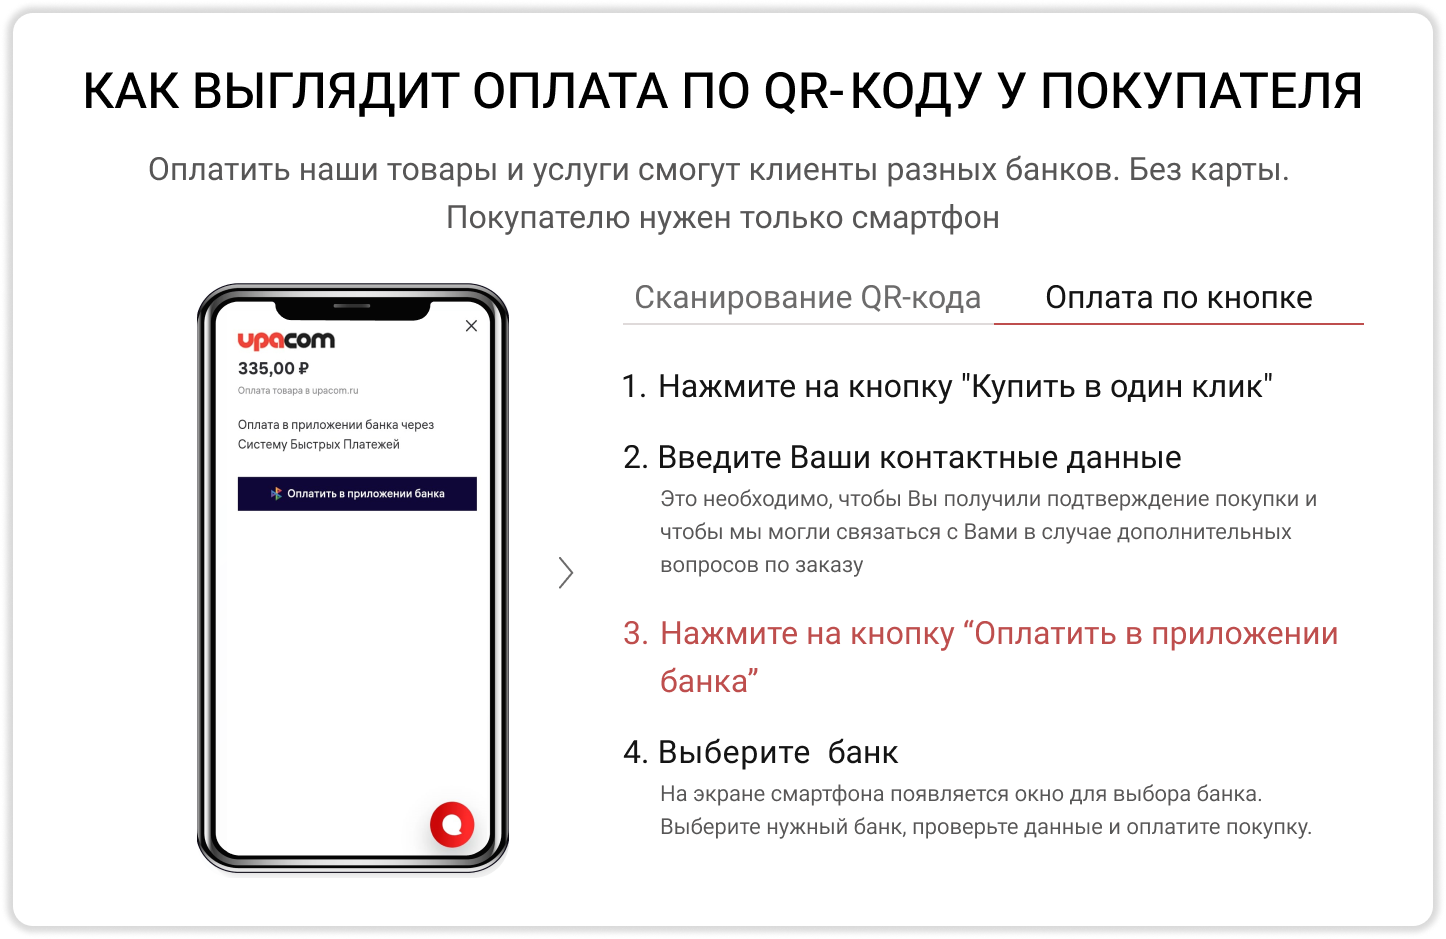

Аппарат для проведения сфокусированной экстракорпоральной ударно-волновой терапииPiezoson 100plus от компании "Richard Wolf" сочетает в себе эффективность и безболезненность за счет использования уникального запатентованного пьезоэлектрического источника ударных волн.

Аппарат для проведения сфокусированной экстракорпоральной ударно-волновой терапии Piezoson 100 plus от компании "Richard Wolf" сочетает в себе эффективность и безболезненность за счет использования уникального запатентованного пьезоэлектрического источника ударных волн. К преимуществам пьезоэлектрического источника ударных волн также относится высокая надежность и долговечность, что делает Ваши инвестиции наиболее оправданным.

Аппарат экстракорпоральной ударно-волновой терапии Piezoson 100plus может использован как для проведения ударно-волновой терапии, так и для выполнения терапии триггерных точек.